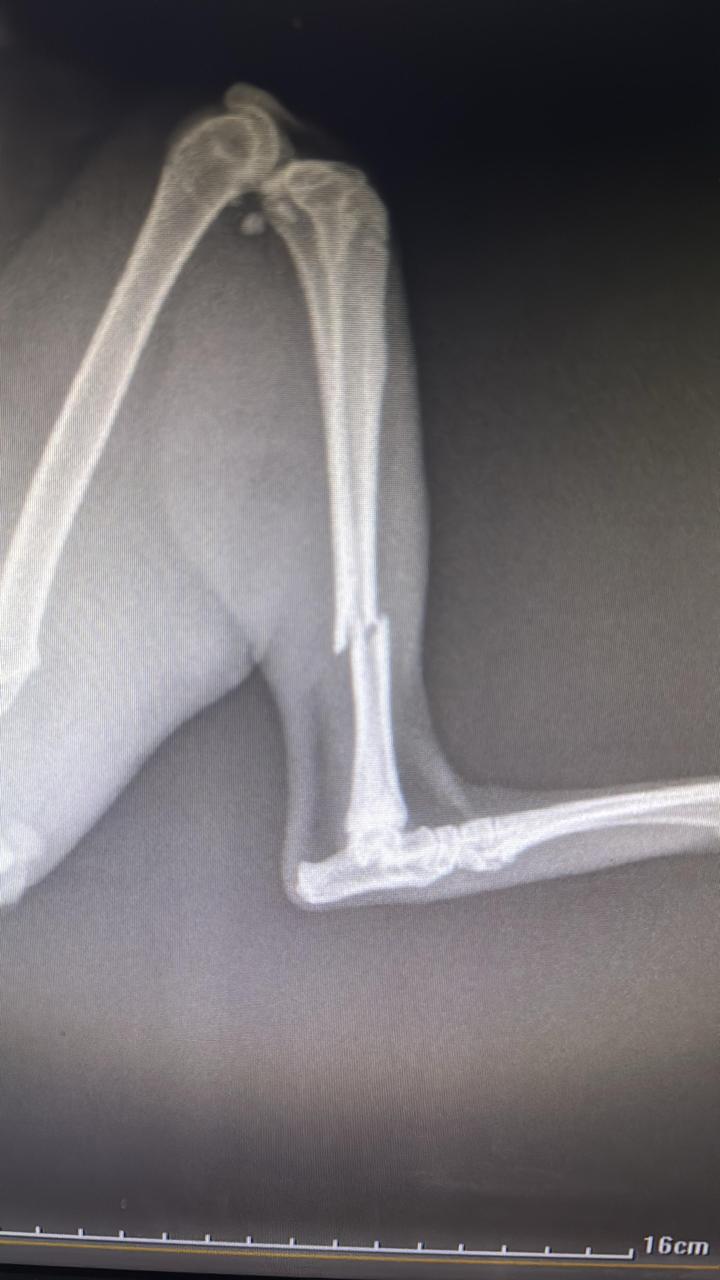

Historia: ¡Hola! Soy Lufi, el capitán pirata. Mi apodo me lo gane porque me rescataron hace tiempo con una pata quebrada y requerí de tratamiento ortopédico para no perderla, me decían que era un pirata por mi pata de palo y mis habilidades para robar lonches y juguetes de otros michis. Actualmente ya estoy totalmente recuperado, vacunado y esterilizado. Soy un michi extremadamente juguetón, curioso y aventurero y me caen muy bien los perros, gatos y niños. Aun recuerdo mi vida de calle y a veces busco escaparme, por lo que tendrás que demostrar que eres mas listo que yo para evitar mis escapes.